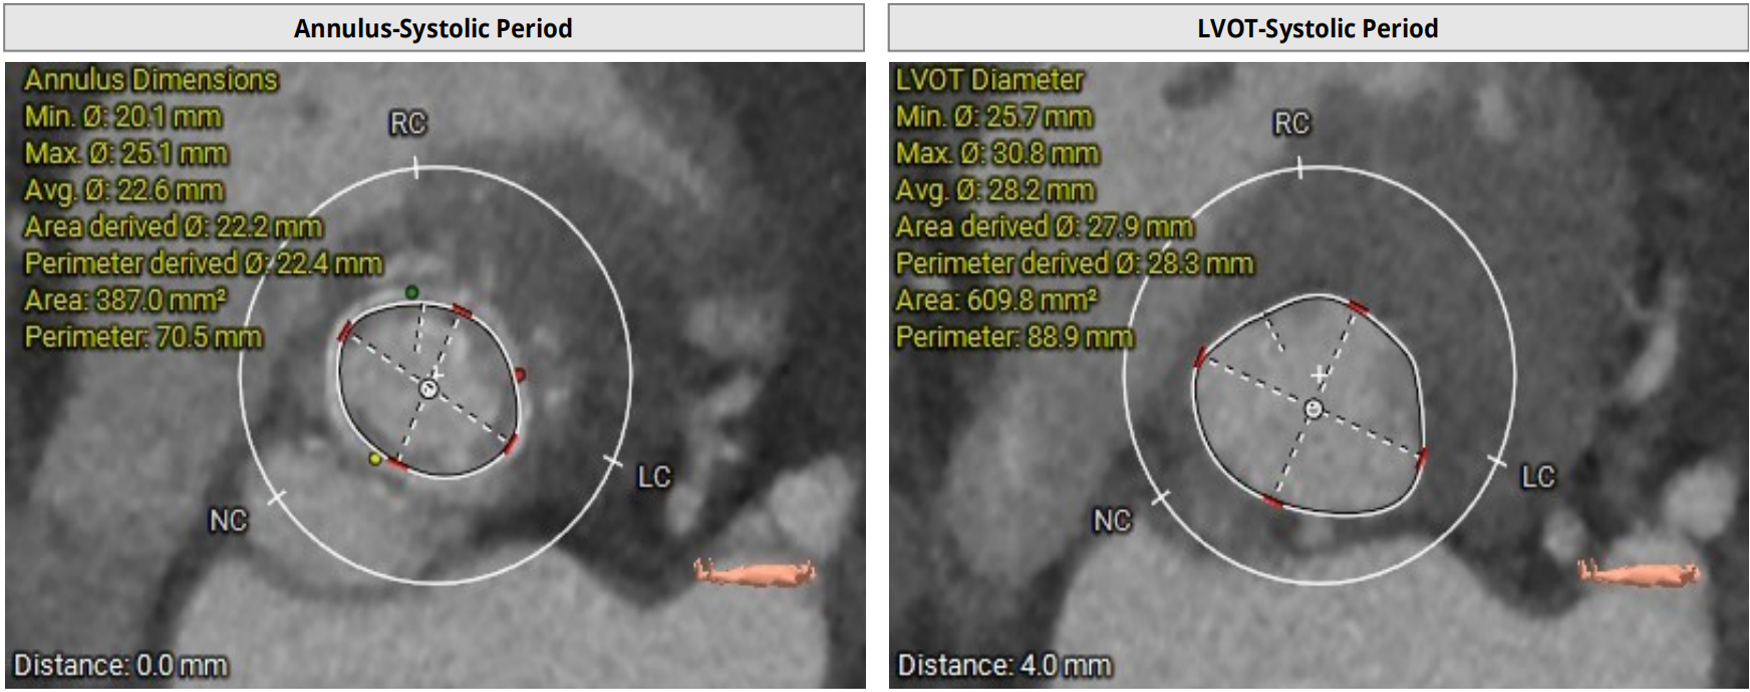

2D echo suggestive of severe aortic regurgitation. CT analysis done and we decided to opt for 24mm TAVR valve

SEV 24 mm was chosen based on CT measurement and bifemoral access was obtained. Carotid filter was placed for cerebral protection.During resheathing of the valve there was sudden circulatory collapse. CPR started and left coronary catheterisation revealed occlusion of left main. Flow was established in LAD with immediate wiring and ballooning. Finally TAVR valve was deployed after LAD flow was established.LCX flow was then resolved and LM bifurcation PCI was done using crush technique Patient was finally discharged in hemodynamically stable condition.